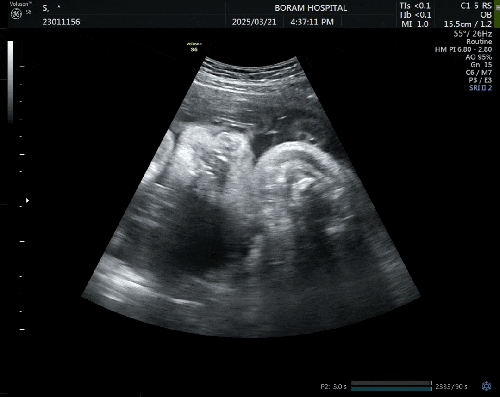

임신일기, 아홉번째: 임신31주 쌍둥이, 정부지원 산후도우미 신청

벌써 31주가 지났다. 병원 갔더니 1.7kg, 1.8kg으로 쌍둥이들 너무 잘 크고 있다. 하품하는 깐둥이 ❤️ 31...